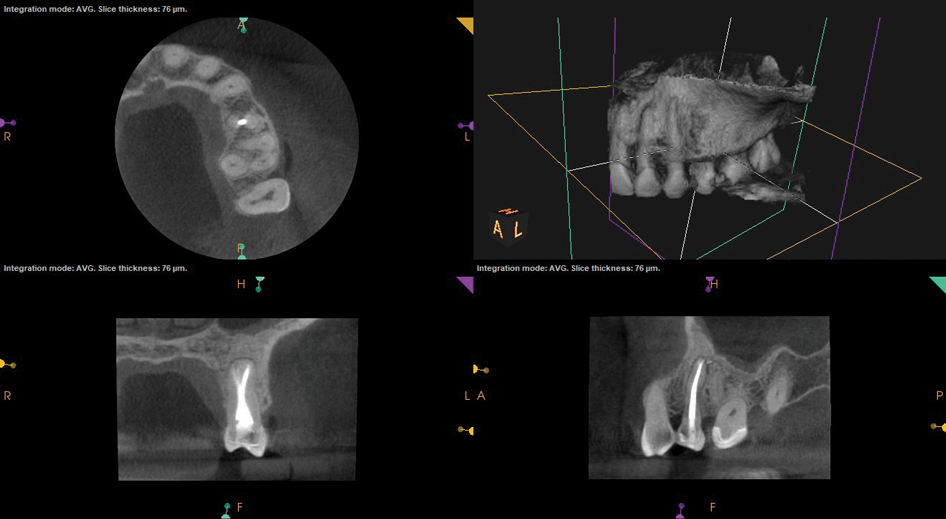

Periapical and CBCT imaging confirmed the presence of apical pathology, as well as a dramatic sinus communication with MSEO (Figure 1 and Figure 2). The diagnosis for tooth No. 13 was pulpal necrosis with asymptomatic apical periodontitis. NSRCT was completed (Figure 3). At the patient's 1-year follow-up appointment, tooth No. 13 remained asymptomatic, her sinusitis was resolved, and complete radiographic healing of both periapical pathology and the MSEO was noted (Figure 4).

Fig 1. Case 1. Preoperative periapical radiograph showing periapical pathology associated with tooth No. 13.

Figure 1

Fig 2. Preoperative CBCT. Note periapical pathology associated with tooth No. 13 communicating with the adjacent maxillary sinus along with associated mucositis.

Figure 2